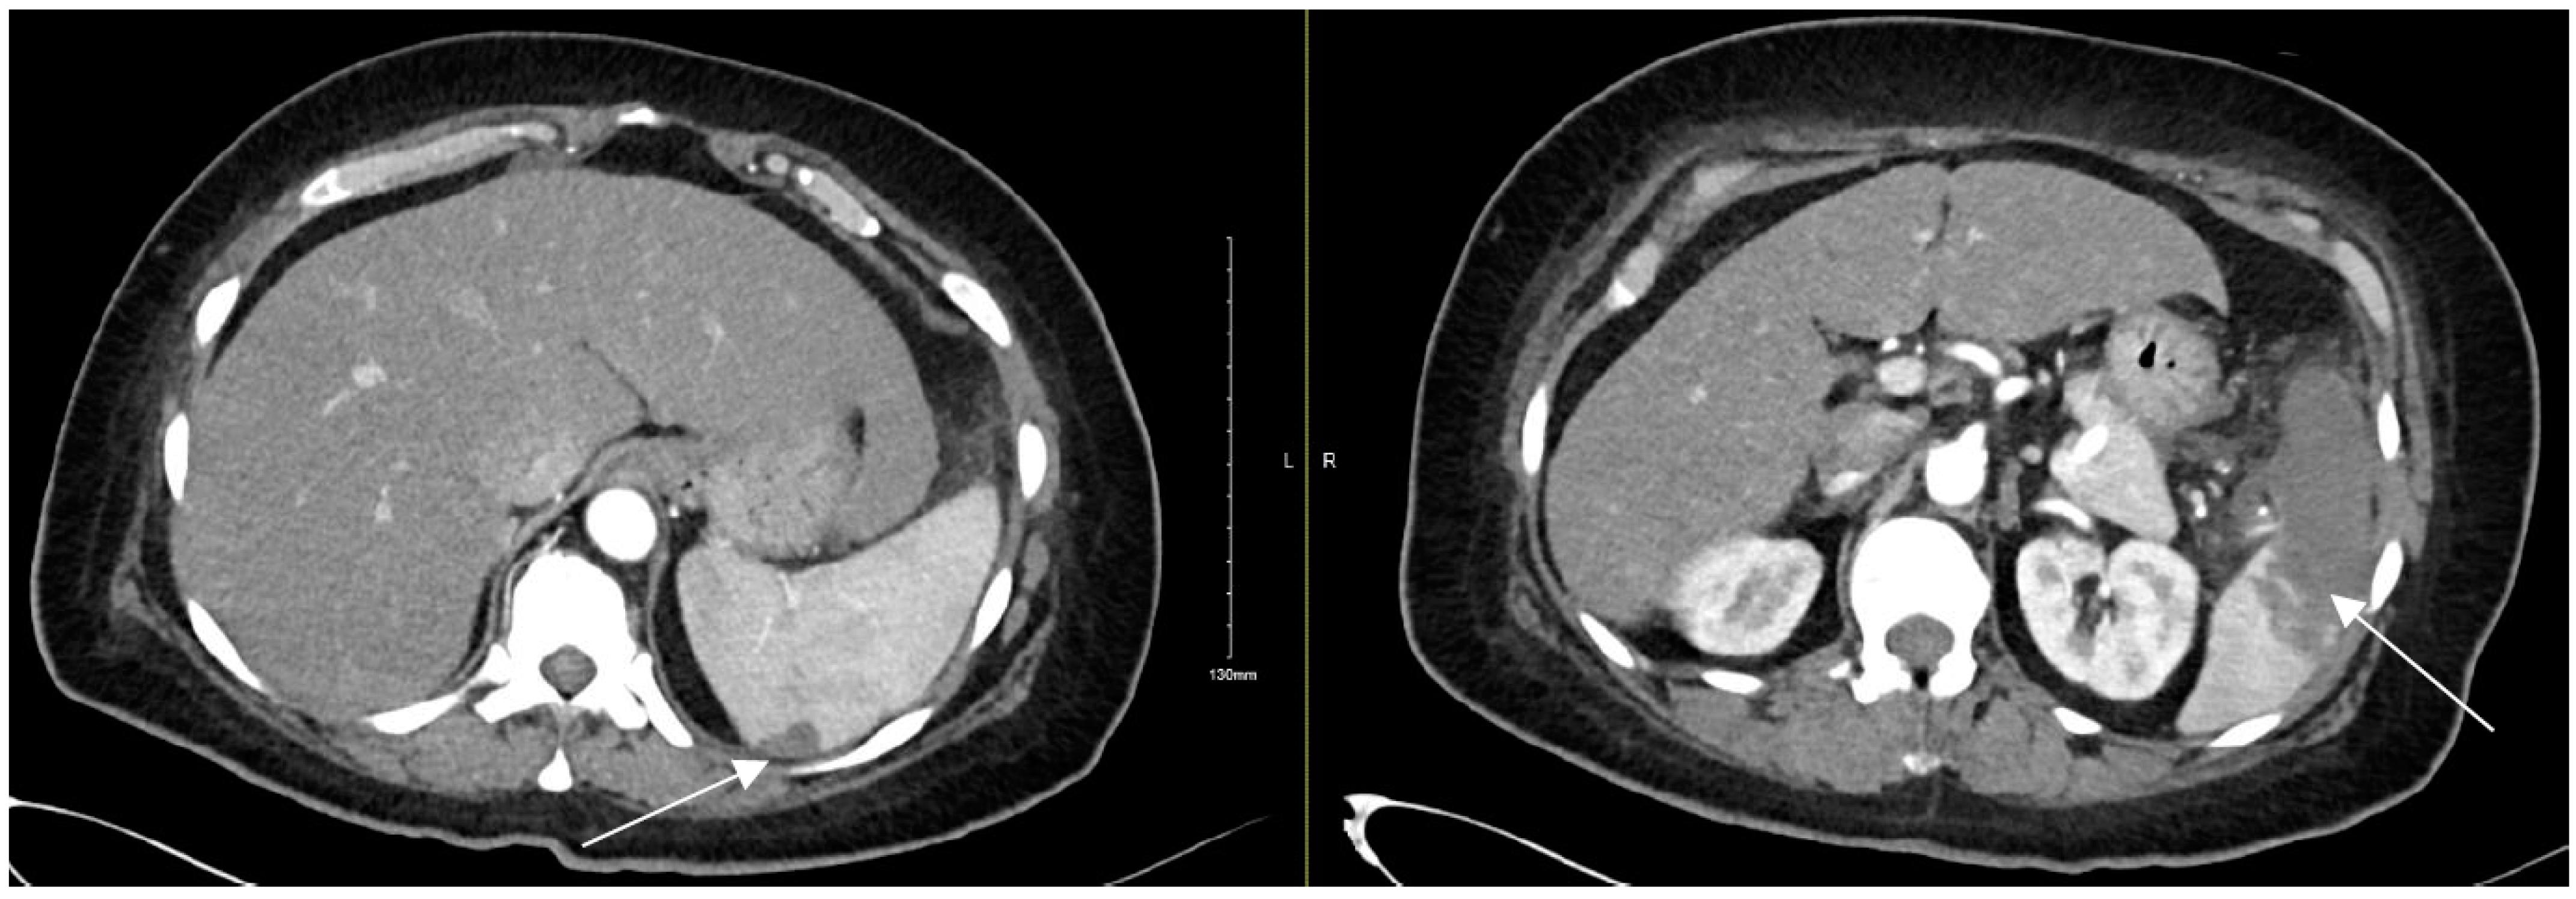

Refractory Salmonella Prosthetic Valve Endocarditis Complicated by Splenic Infarction and Aortic Pseudoaneurysm in a Patient with Double Prosthetic Valves: A Case Report

2. Case Presentation